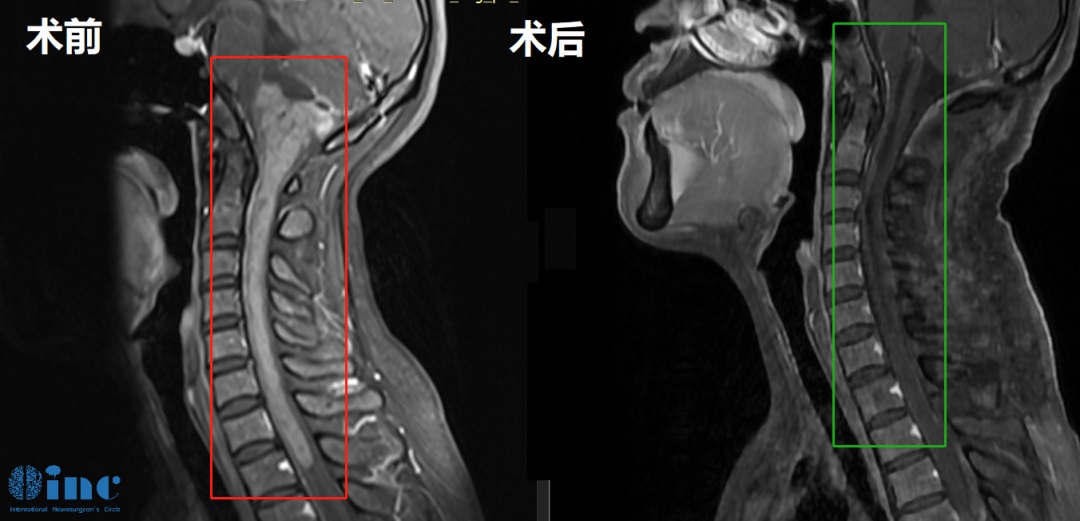

30岁女性-延髓-颈髓海绵状血管瘤

34岁男性-脑干延髓-颈髓室管膜瘤WHO2级

术后一个多月,患者行走自如已基本恢复正常生活。

5岁女孩脊髓-脑干毛细胞星形细胞瘤

术后一年多,琦琦回归校园,她一直努力坚持做训练,运动是她每天的必修课,家里的沙发上、椅子旁、地板垫子上……随处可见她运动的身影!